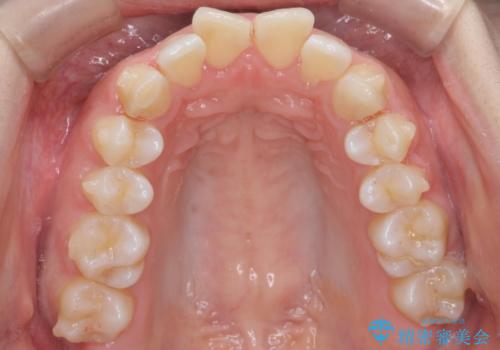

- 前歯のがたつきと突出を主訴に来院。

歯を抜かずに非抜歯で治療しました。